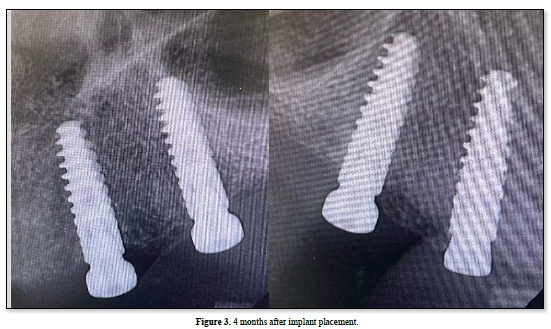

Preoperative orthopantomogram and CBCT were taken in order to evaluate the amount of bone in the ideal position of implant placement. Surgery for implant placement was performed under local anesthesia following a standard operation protocol. A mid-crestal incision in the attached gingiva of the upper edentulous alveolar crest from the canine area of the quadrant until the premolar area on each side with two vertical releasing incisions was performed, after reflecting the mucoperiosteal flap and exposure of the bone, 4 implants were placed in the upper arch by an oral implantologist in order to construct implant-supported maxillary overdenture (Figure 2). Postoperative orthopantomogram after all four implants placement (AnthyogerAxiom®BL PX 3.4 x 12mm), All implants were placed with the same recommended torque of <35 Ncm. Then, healing abutments were placed and the passively mobilized mucosa was closed with resorbablevicryl sutures with a simple interrupted technique. A standard oral antibiotic regimen, mouthwash, and pain killers were applied after implant placement, and post-operative instruction was given. The patient was clinically evaluated after 2 weeks to assess healing. The patient was recalled after 4 months to evaluate implant success to start with the prosthetic superstructure. A periapical radiograph showed full osseointegration with no crystal bone loss (Figure 3). No pain was reported. As well as, no mobility or abnormal pocket depth was noticed.